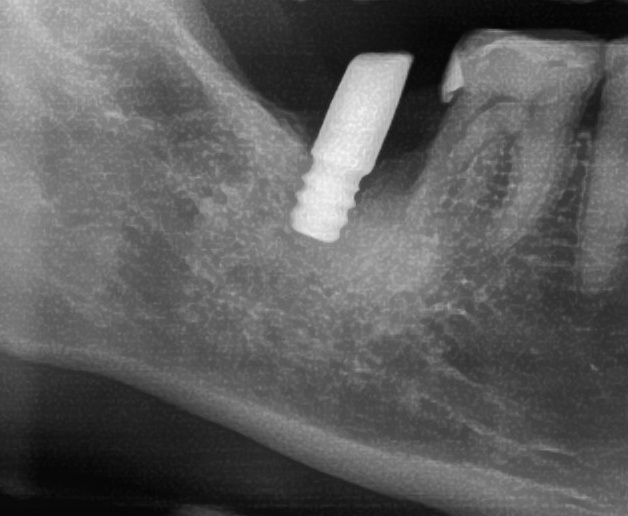

開けた穴に、専用道具を使ってネジを締めるように長さ2センチ程のインプラントを骨に埋め込んでいきます。

しっかりとインプラント埋め込まれた後は、動揺がないか、噛んだ時に当たらないかなどを確認して、最後にパノラマ写真を撮影して今回のオペは終了となりました。